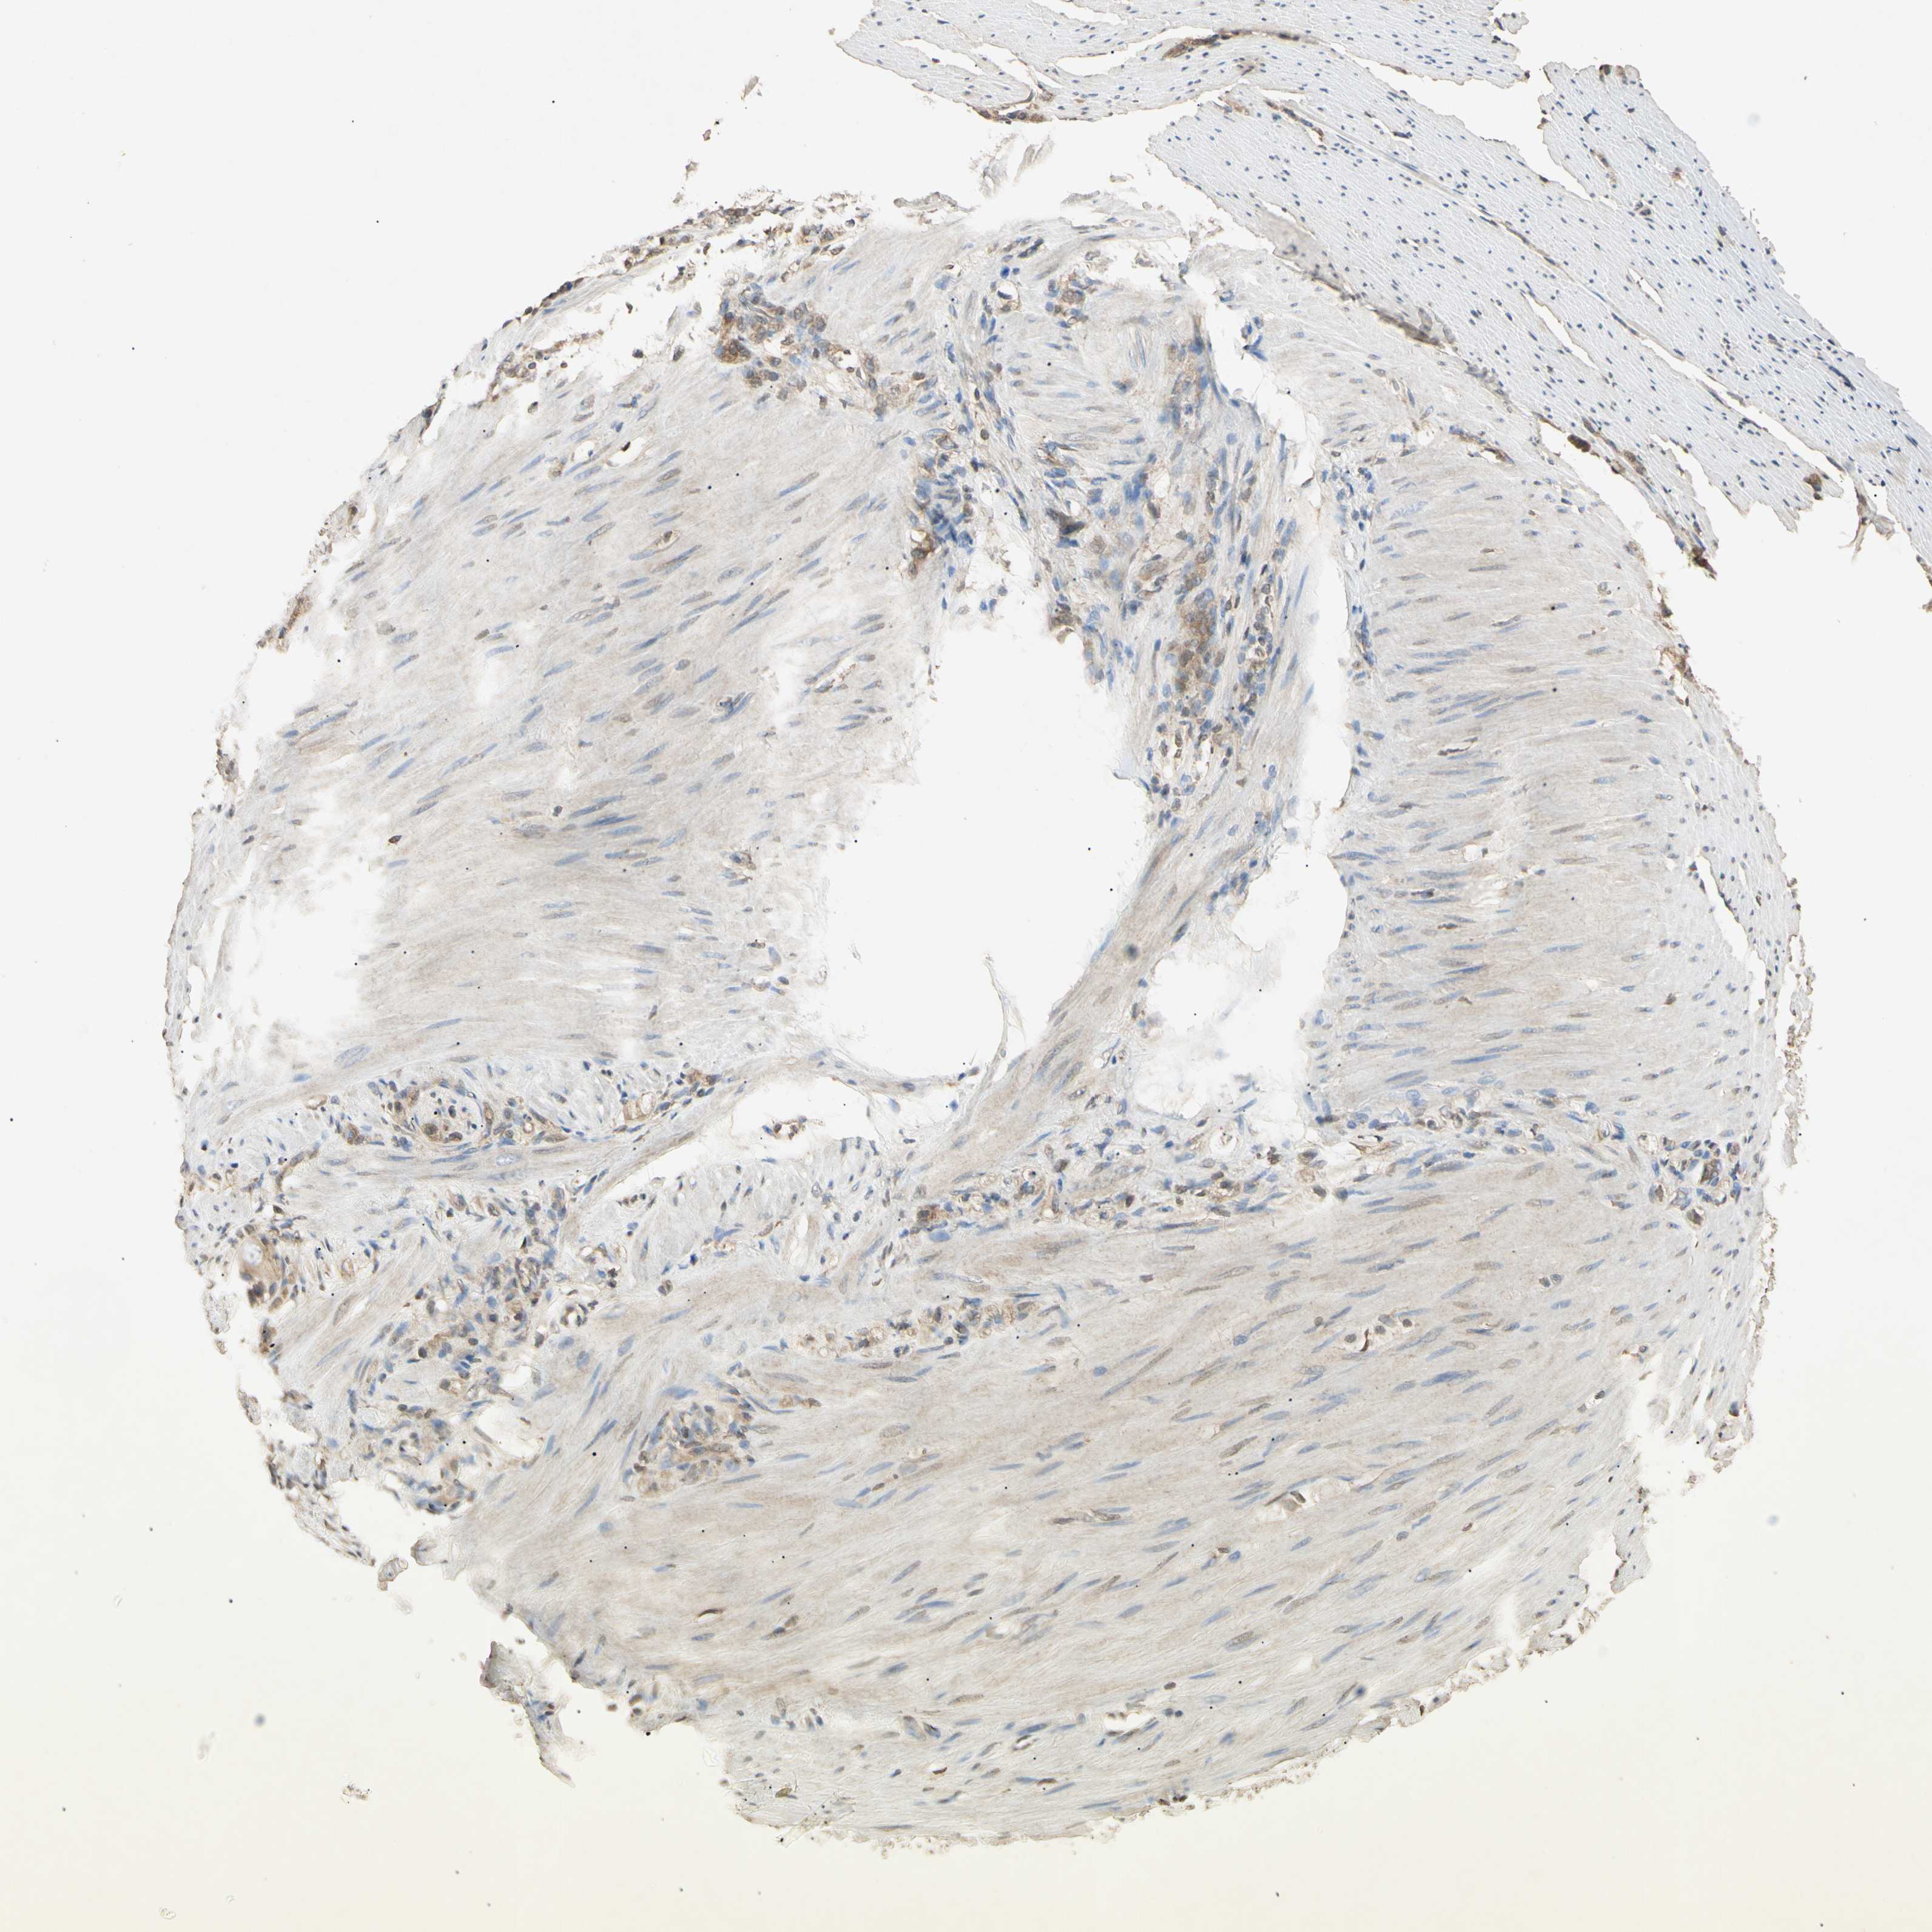

STOMACH CANCER - Protein expressioni

A mouse-over function shows sample information and annotation data. Click on an image to view it in a full screen mode. Samples can be filtered based on level of antibody staining by selecting one or several of the following categories: high, medium, low and not detected. The assay and annotation is described here.

Note that samples used for immunohistochemistry by the Human Protein Atlas do not correspond to samples in the TCGA dataset.

Antibody stainingi

Antibody staining in the annotated cell types in the current human tissue is reported as not detected, low, medium, or high, based on conventional immunohistochemistry profiling in selected tissues. This score is based on the combination of the staining intensity and fraction of stained cells.

Each image is clickable and will lead to virtual microscopy that enables deeper exploration of all samples and also displays staining intensity scores, fraction scores and subcellular localization as well as patient and tissue information for each sample.

Antibody CAB009729

Staining

High

Medium

Low

Not detected

Intensity

Strong

Moderate

Weak

Negative

Quantity

>75%

75%-25%

<25%

None

Location

Nuclear

Cytoplasmic/membranous

Cytoplasmic/membranous,nuclear

Adenocarcinoma, NOS

Adenocarcinoma, High grade